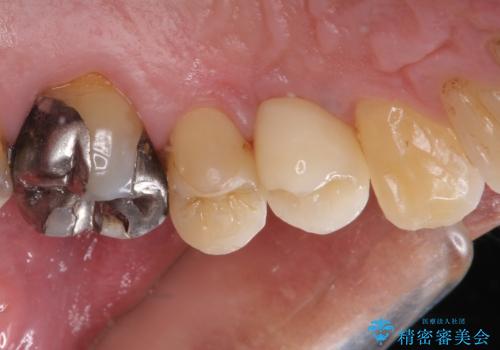

割れてしまった小臼歯 インプラントによる補綴治療

- 他院で抜歯が必要と診断され、再度診断を希望して来院された患者様です。

顕微鏡下で診察を行ったところ、歯根が垂直に破折していたため、抜糸してインプラントによる補綴治療を行うこととしました。

より審美的で、より機能的に優れた治療をご希望とのことであったので、ジルコニアカスタムアバットメントを用いたインプラント治療を行うこととしました。